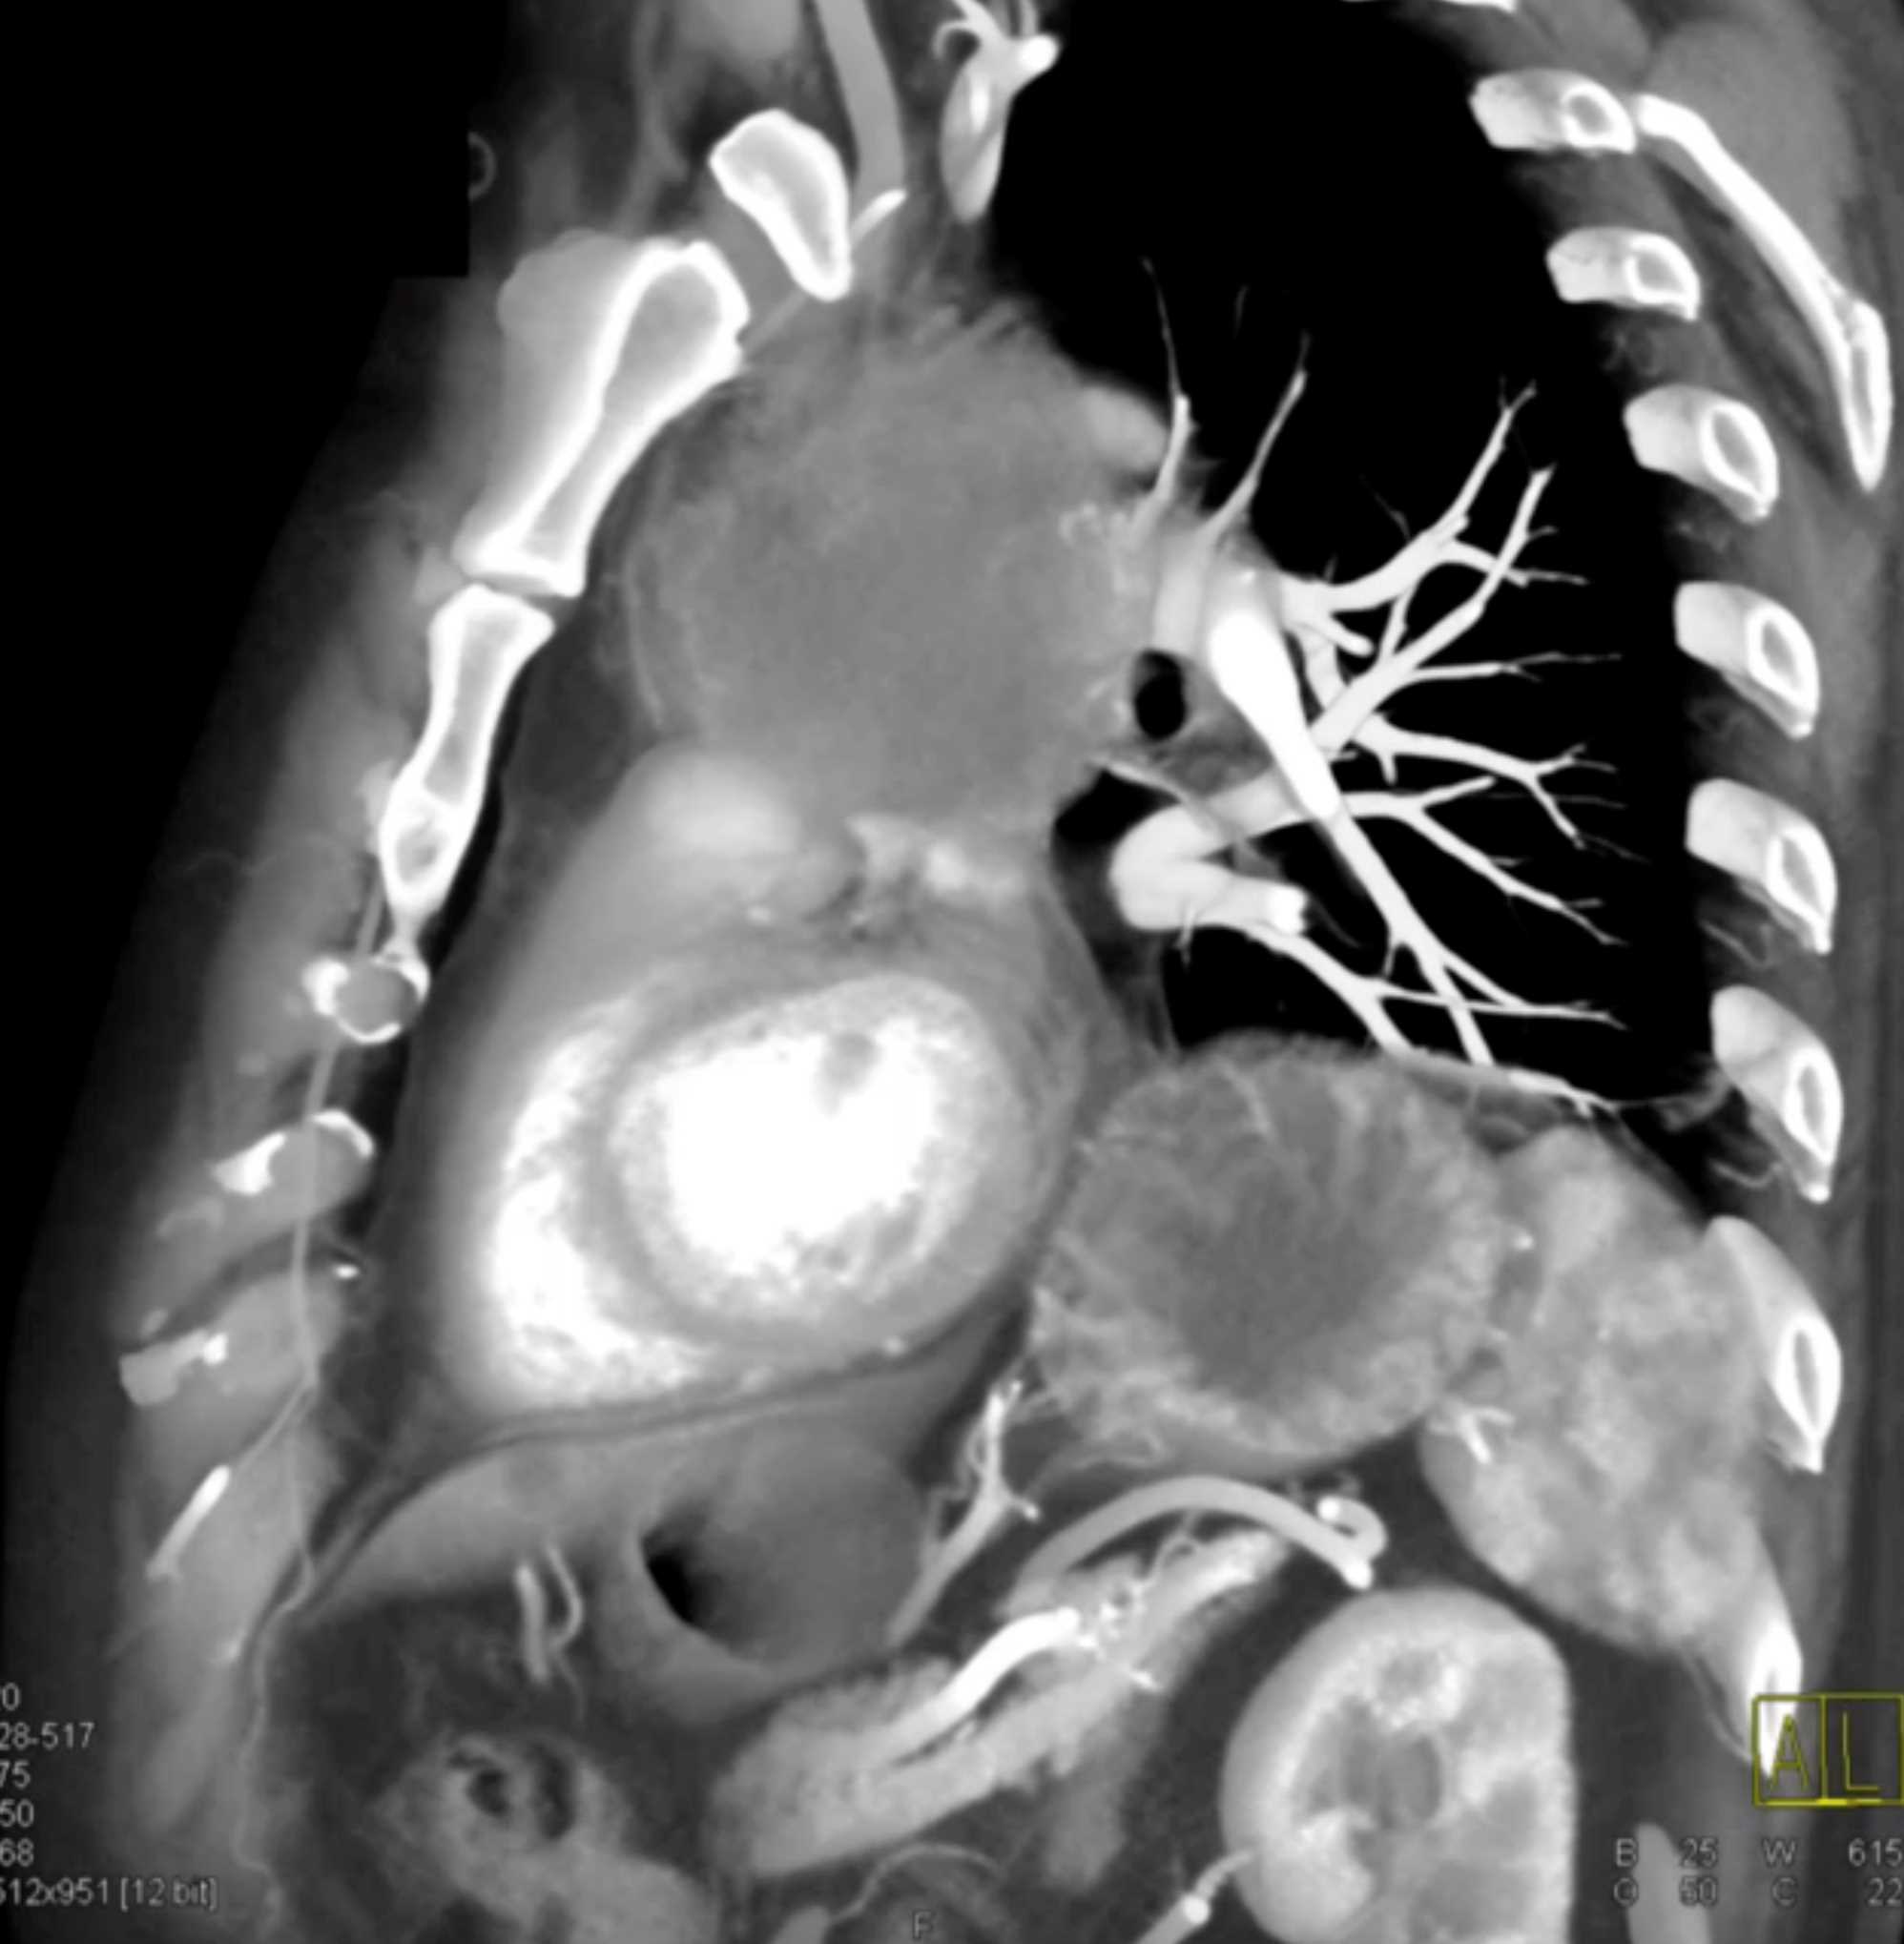

Thymic Carcinoma